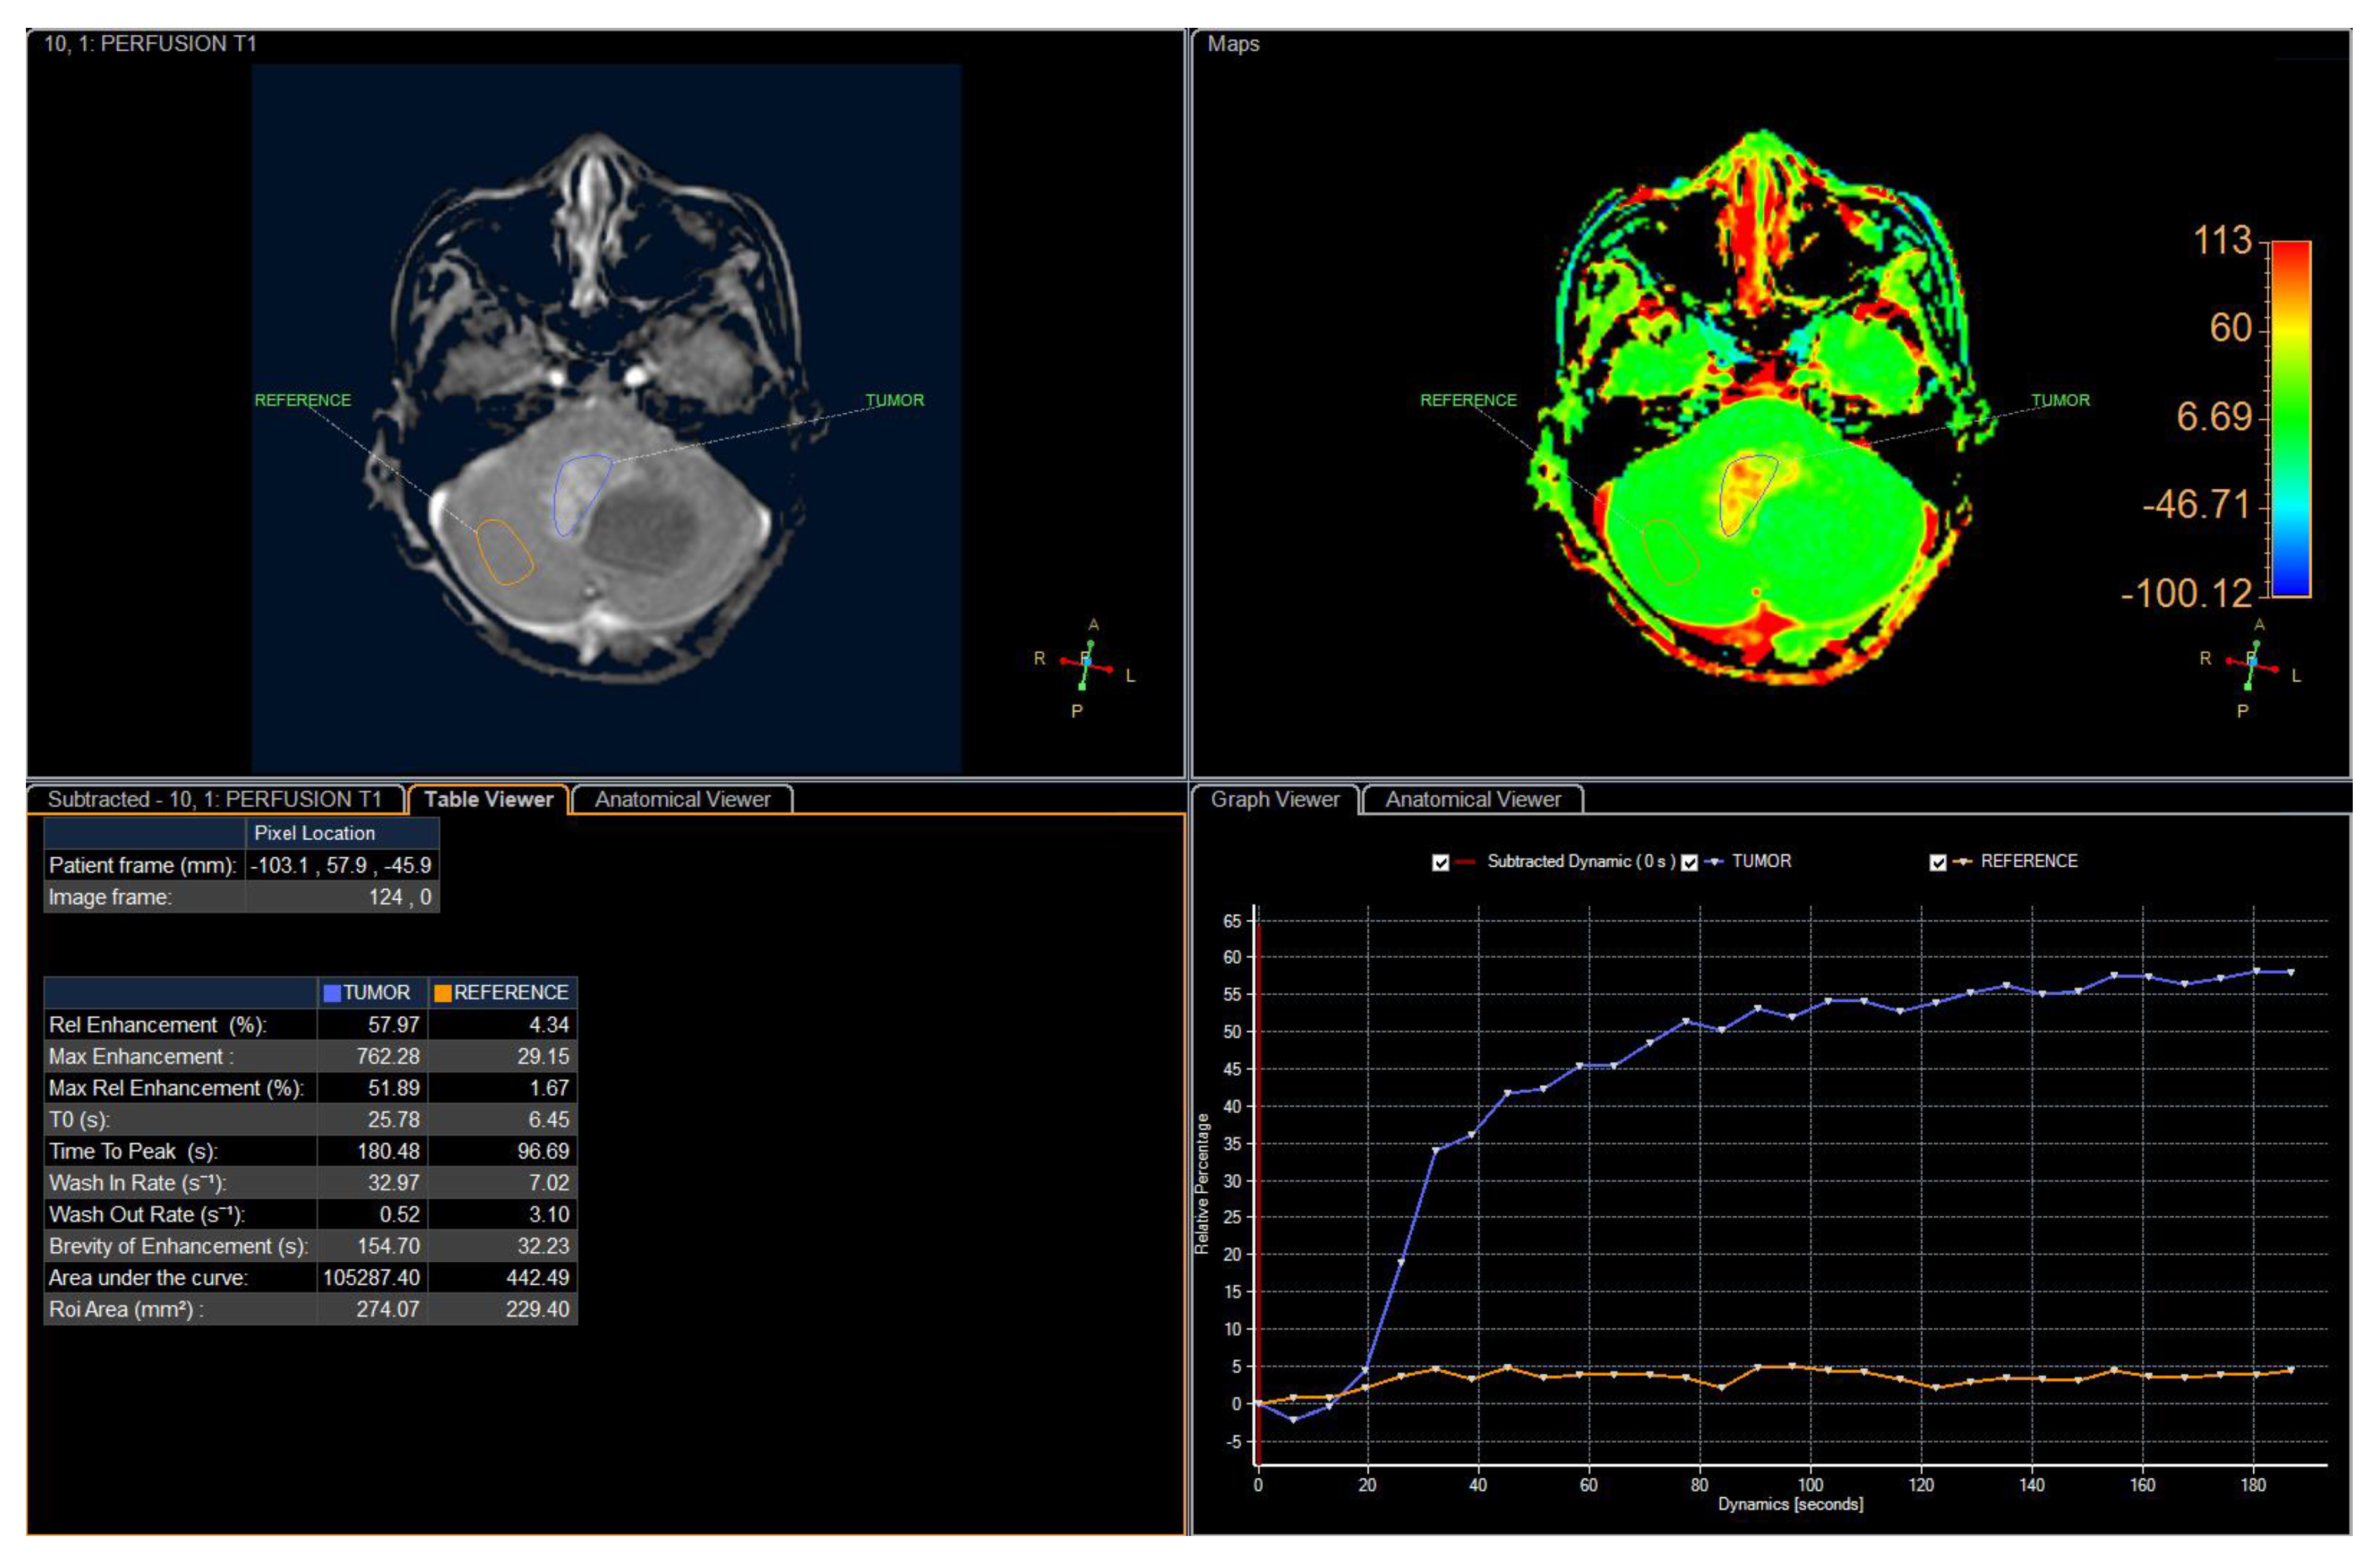

2. Case Presentation